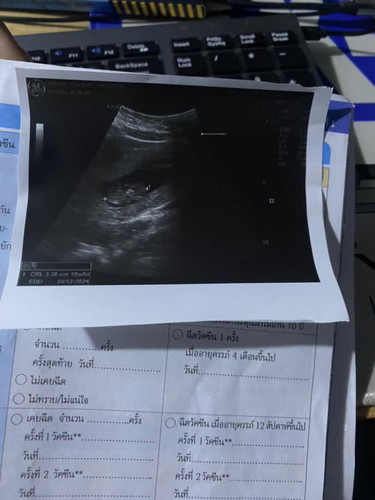

มีแม่ๆคนไหนตั้งครรภ์แรกแล้วท้อง10wตัวจิ๋วแบบนี้ไหมคะ

ดูจากขนาดของลูก + จำนวน week ที่ระบุในภาพซาวน์ก็อยู่ในเกณฑ์ปกติของทารก 10 week นะคะ ... ไม่ต้องกังวลค่ะเรื่องกินอะไรไม่ได้เพราะในช่วงนี้ทารกจะได้รับสารอาหารจากถุงไข่แดงอยู่ค่ะ

ขอเค้า 9w 2.23cm